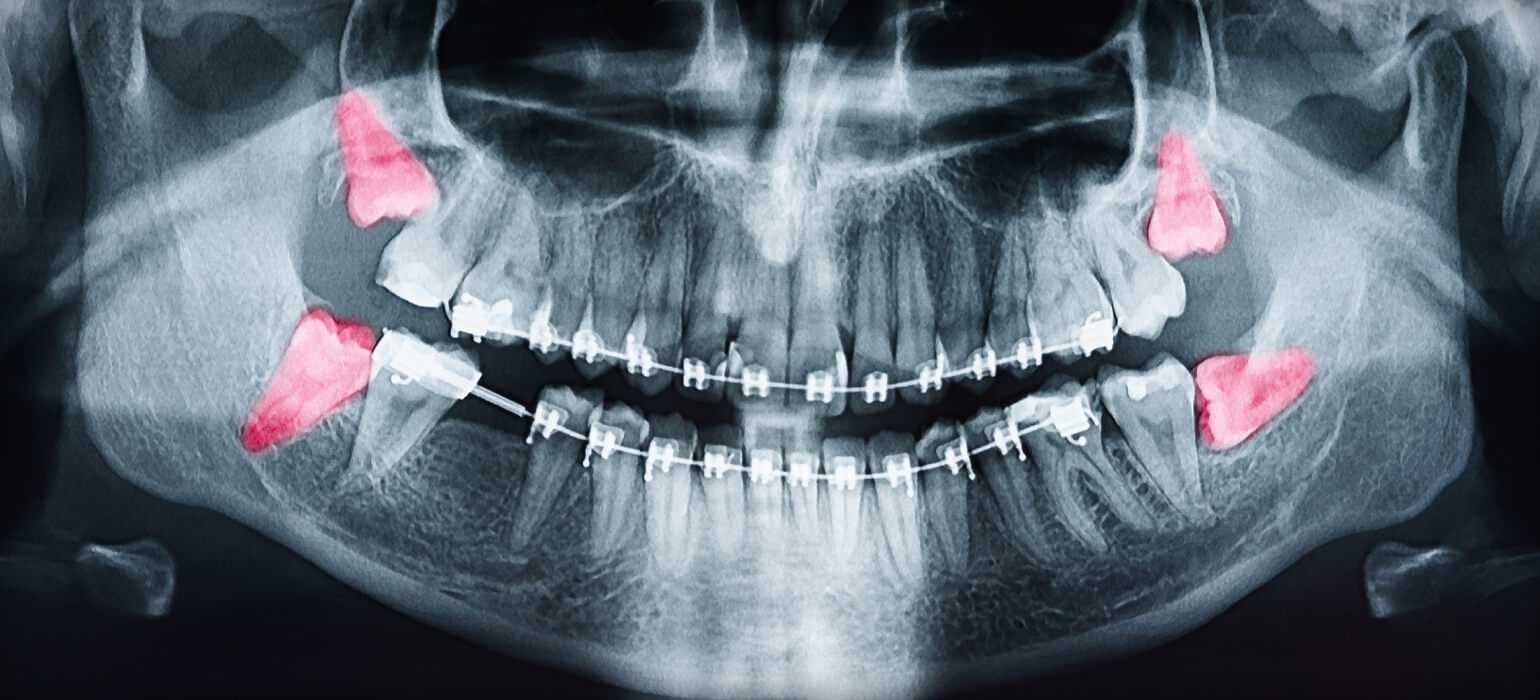

Xray showing wisdom teeth coming in

Wisdom teeth are the third and final set of molars that erupt in the back corners of the upper and lower normal adult mouth. Unfortunately, most people experience problems from wisdom teeth; in most cases, this is because the teeth erupt too close to existing permanent teeth, causing crowding, improper bites, and other problems.

If wisdom teeth are causing a problem, this could mean that they are impacted.  Impacted wisdom teeth can be extremely painful, as well as harmful to your oral health. Symptoms are easy to spot and include severe discomfort, inflammation, and in some cases infections.